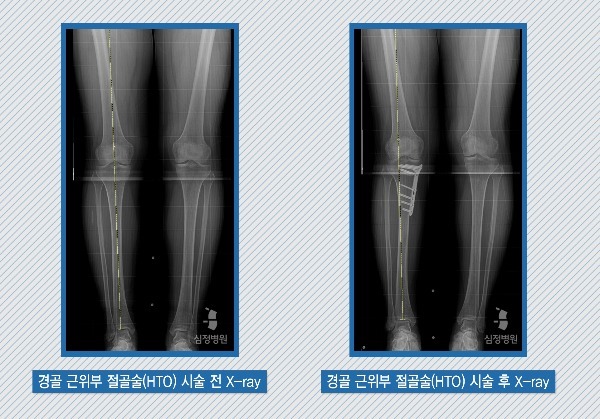

심한 'O'형 변형의 경우, 뼈의 변형을 교정하는 수술을 시행하거나 관절면이 심하게 파괴된 경우는 인공 관절 수술을 시행해야 합니다. 인공 관절 수술은 심하게 마모되어 변형된 관절을 의료용 합금과 플라스틱으로 만든 인공관절로 바꾸어 잘 걸을 수 있도록 돕는 수술입니다.